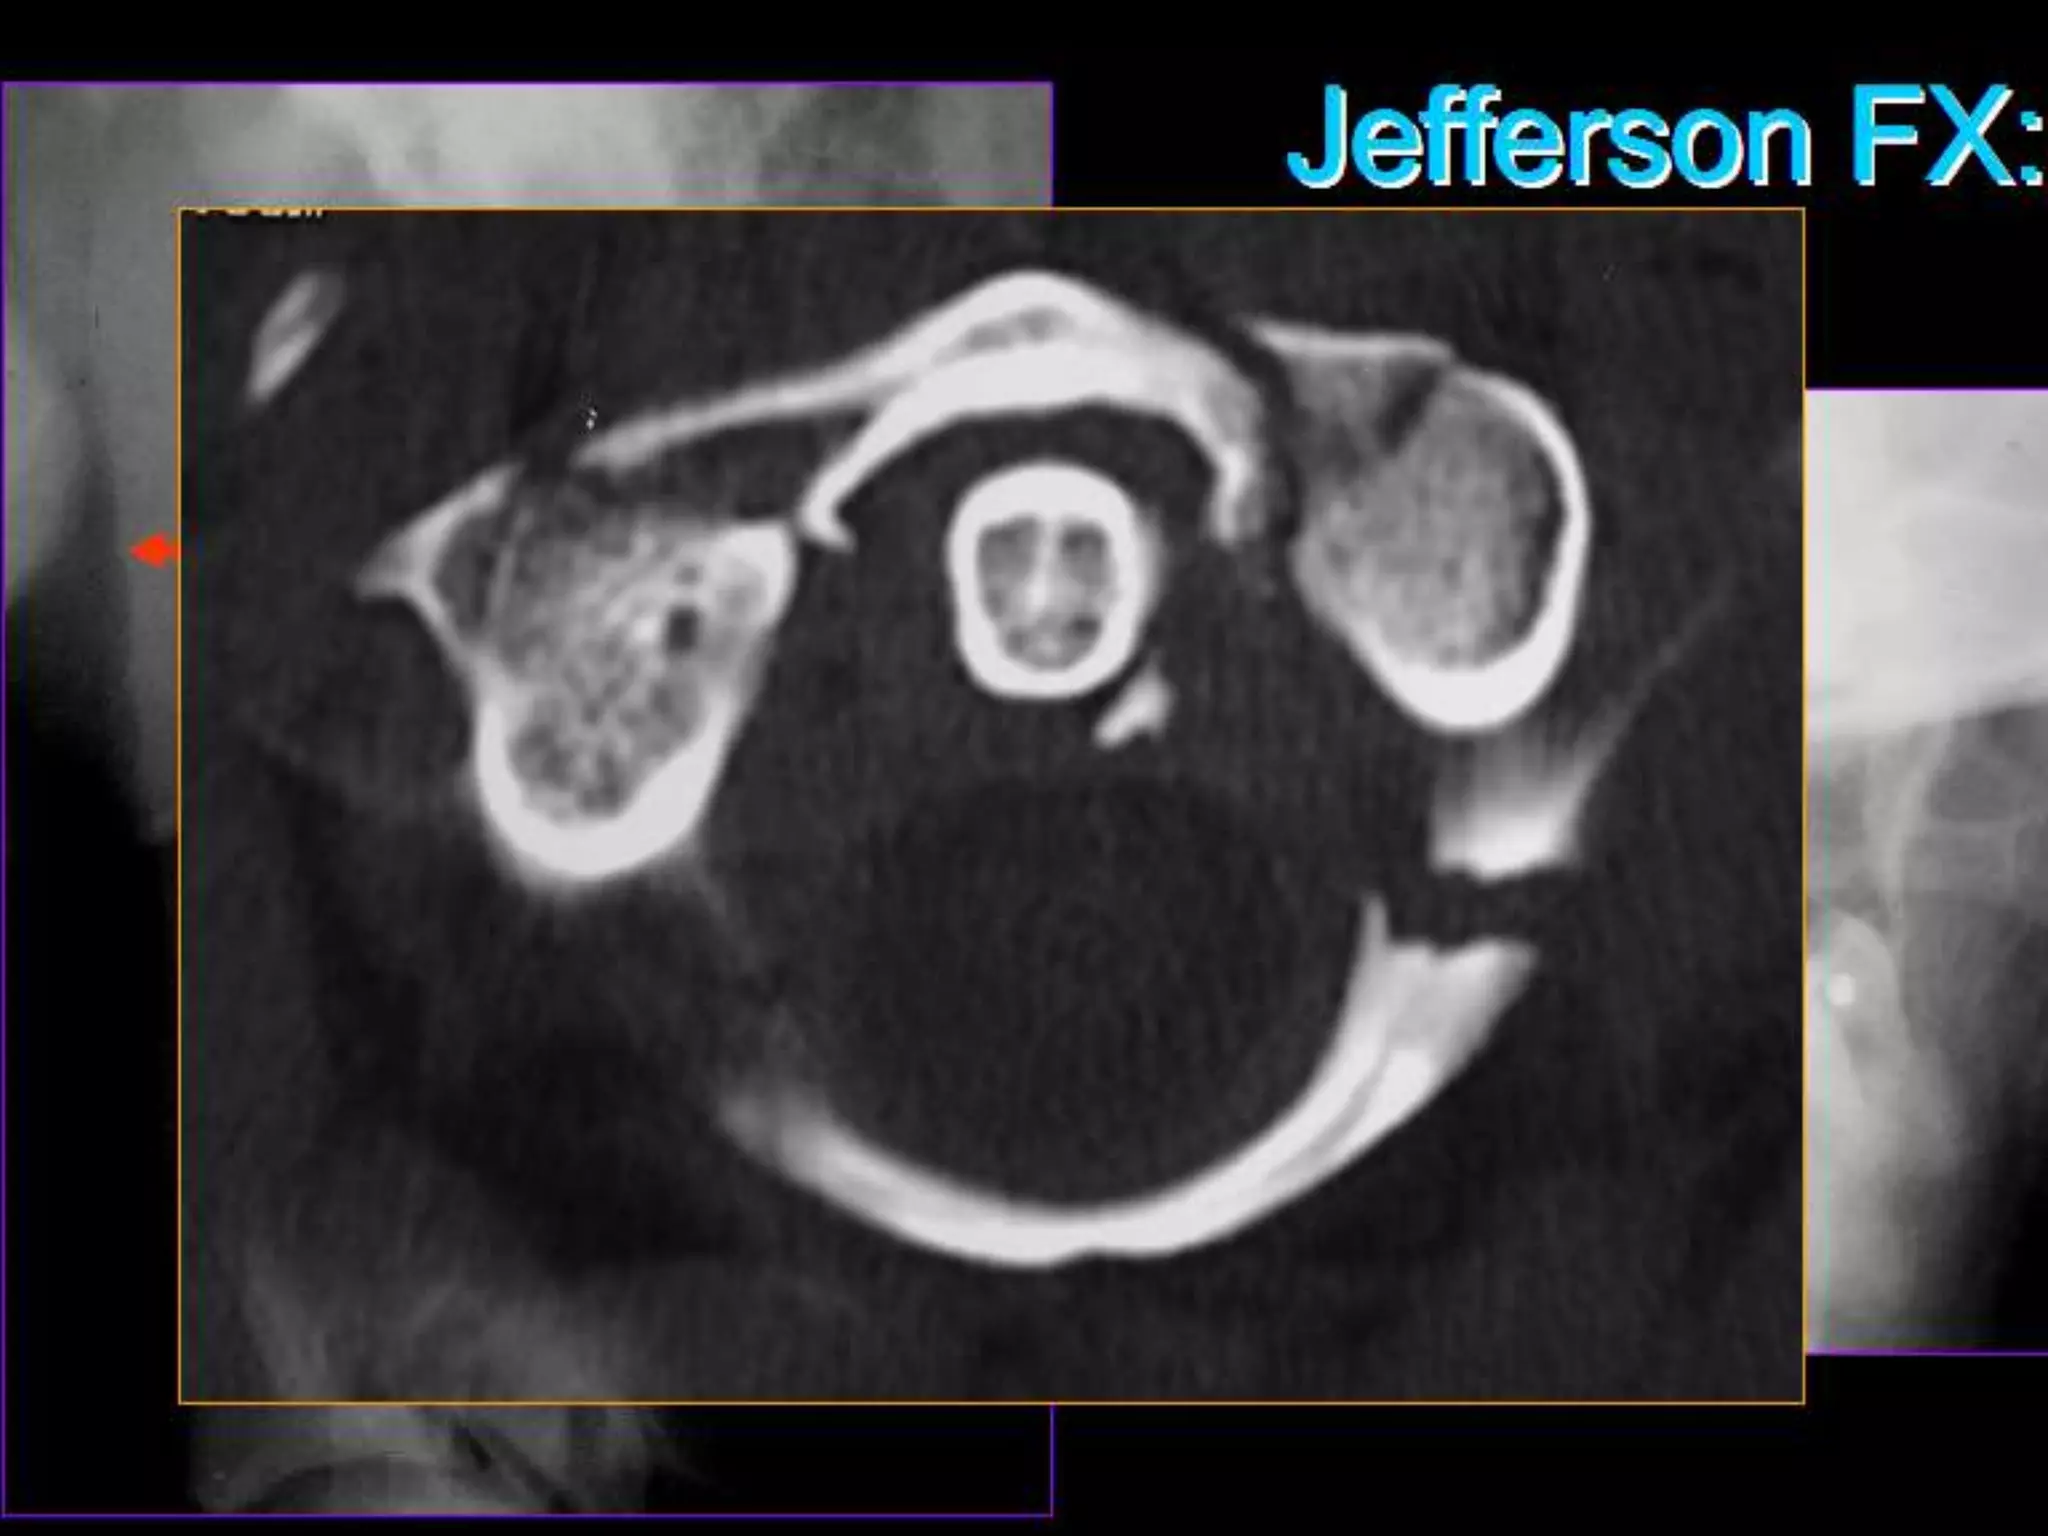

1. Jefferson fracture.

2. Burst fracture.

Jefferson Fracture:

• Splitting of C1 ring with fracture of both the

anterior and posterior arch

– may result from a single break in each arch

(anterior and posterior)

– bilateral or unilateral

• Centripetal displacement fragments

• 50% associated fractures

– 33% = axis fractures

• no neurologic deficit

• Transverse atlantal ligament intact or not

• UNSTABLE

Vertical Compression(Axial Load). •Force delivered to top of skull through the occipital condyles to the cervical spine at the instant that the cervical spine is straight • Injury Patterns: 1. Jefferson fracture. 2. Burst fracture.

• 41.

Jefferson Fracture: •Splitting of C1 ring with fracture of both the anterior and posterior arch – may result from a single break in each arch (anterior and posterior) – bilateral or unilateral • Centripetal displacement fragments • 50% associated fractures – 33% = axis fractures • no neurologic deficit • Transverse atlantal ligament intact or not • UNSTABLE